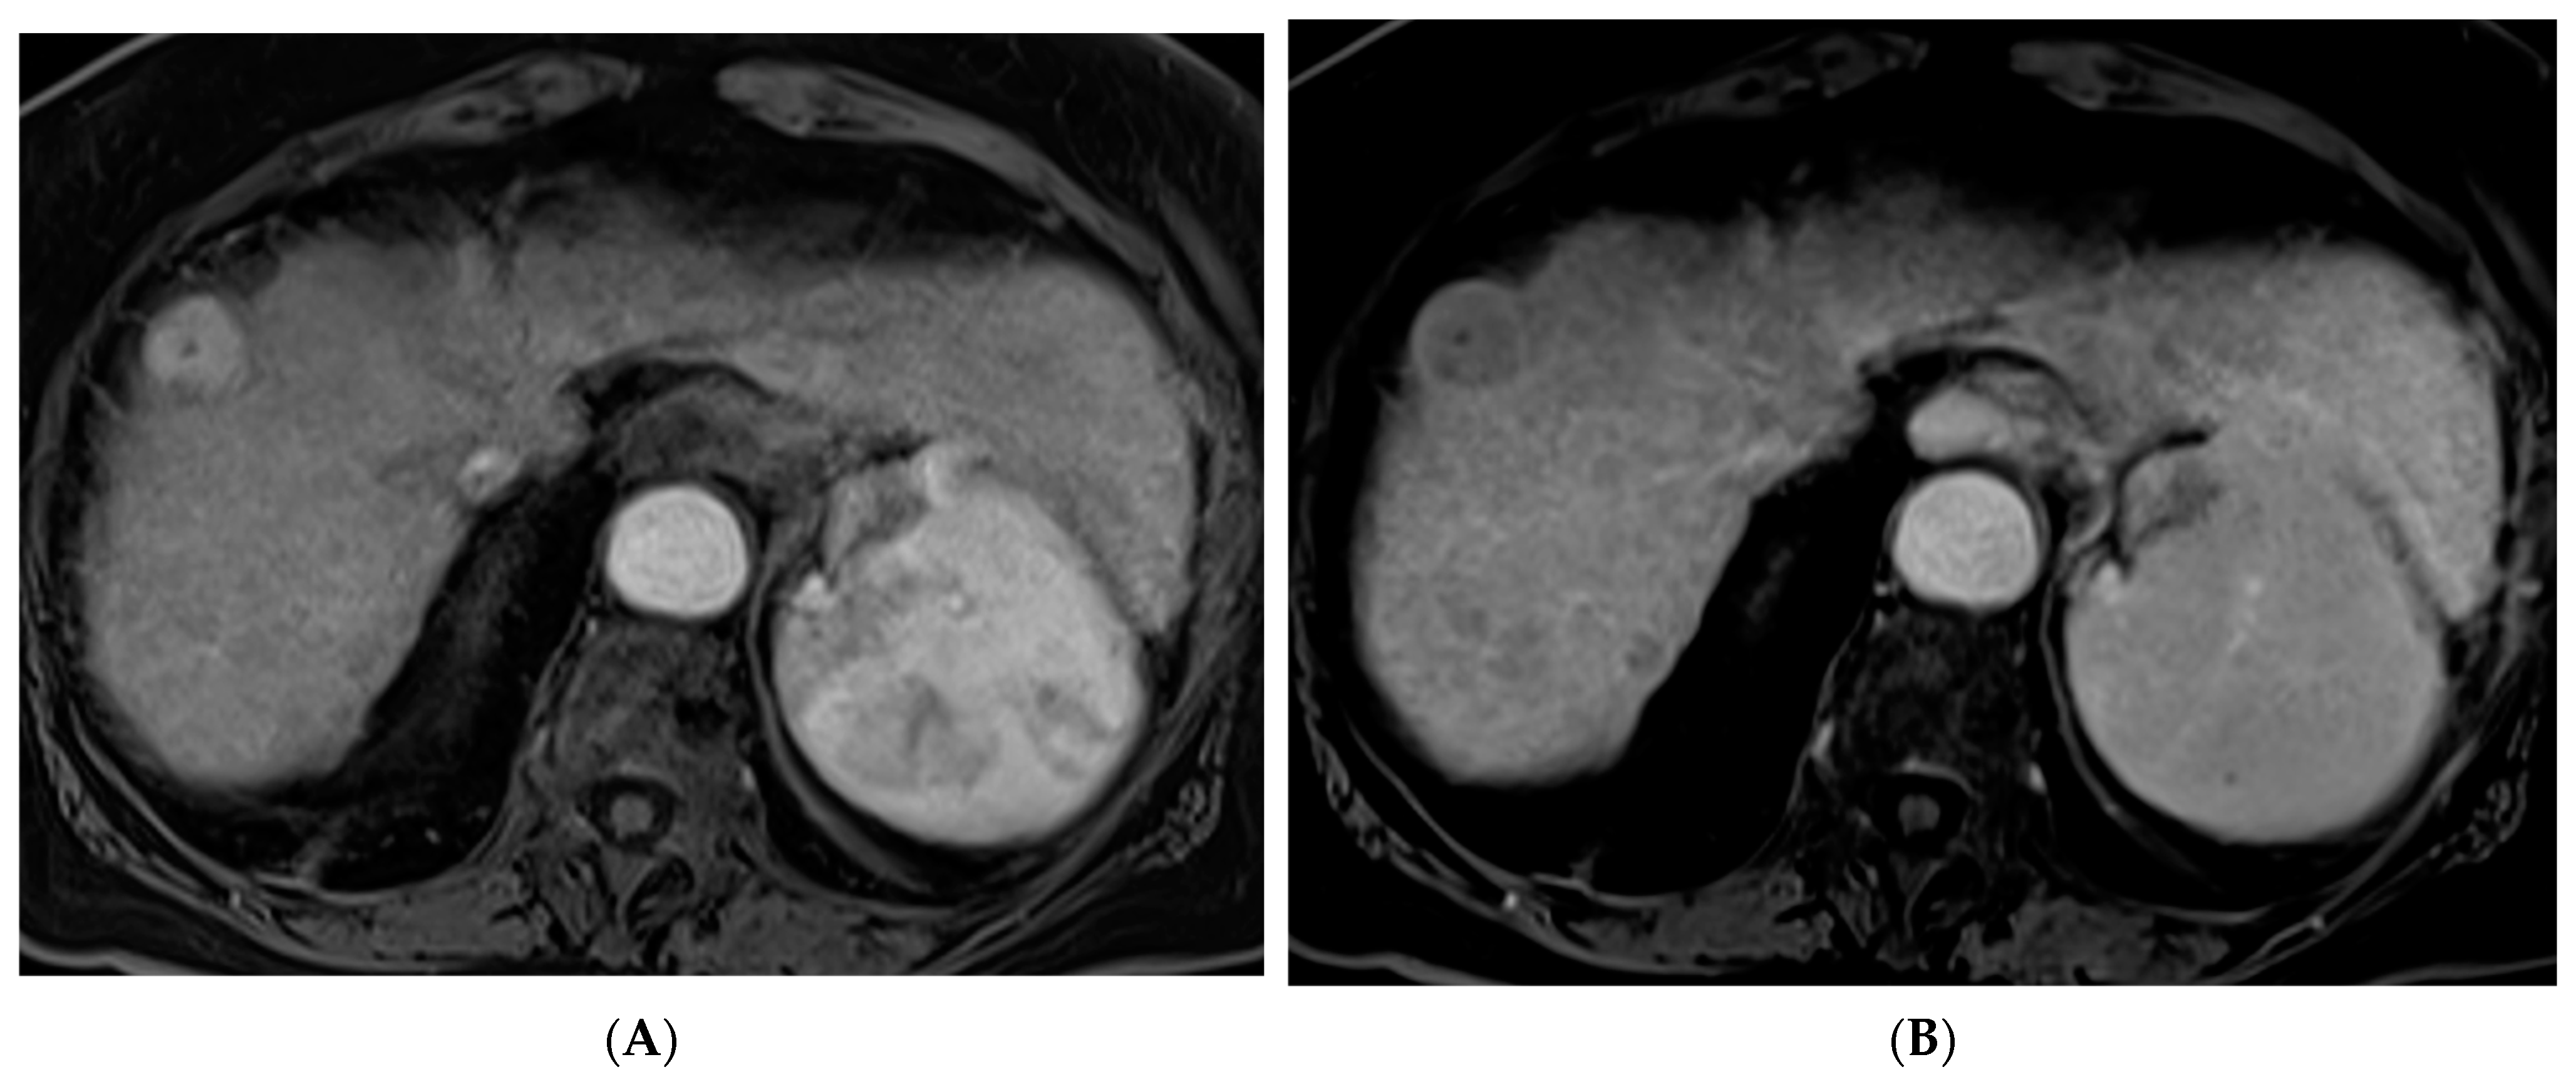

Figure 1. 66-year-old woman with cirrhosis secondary to autoimmune hepatitis and HCC, treated with microwave ablation. (A) Arterial phase MRI showing a 3.5 cm arterially enhancing mass in the periphery of segment 7. (B) Delayed phase MRI demonstrating washout of the mass. Intraprocedural axial (C) and coronal (D) CT images demonstrating probe placement bracketing the mass. (E) Arterial phase MRI one month post ablation showing no residual viable tumor. (F) Arterial phase MRI one year post ablation demonstrating no residual or recurrent viable tumor and involution of the ablation cavity.

Percutaneous ablation is a curative option for patients with very early stage (BCLC 0) or early stage (BCLC A) HCC tumors < 3 cm who are not otherwise candidates for liver transplantation or resection [7]. Various techniques have been developed including RFA, MWA (Figure 1), cryoablation, and irreversible electroporation (IRE). These techniques require the tumor to be in a favorable location with a margin of normal liver tissue between the tumor and a critical structure. RFA is a heat-based technique that was developed alongside the electrocautery knife used by surgeons [8]. RFA involves creating a closed-loop-circuit with an RF electrode, generator, and grounding pads to produce an alternating current that agitates ions in the tissue leading to heat generation [8]. RFA is susceptible to the heat sink effect whereby adjacent vessels can dissipate heat and thus affect the ability to generate the necessary temperature for tumor necrosis, which is one of the pitfalls of this technique [8]. When compared with surgical resection, RFA has demonstrated similar local control and long-term survival with a significantly lower rate of complications as well as a shorter length of hospital stay [18,19,20].

MWA involves producing high frequency oscillating electromagnetic fields which lead to the rapid oscillation of water molecules and the generation of heat. This technique generates heat with a wider zone of the primary heating and is less susceptible to the heat sink effect than RFA. Therefore, higher temperatures can be achieved with a shorter treatment duration, in some cases providing benefit over RFA [8]. MWA has been shown to result in better 5-year survival when compared with RFA for tumors larger than 3.5 cm [21].